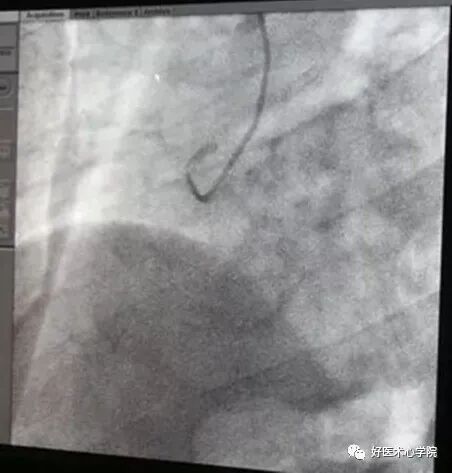

造影导管头端塞入鞘管头,送入导丝,外露导丝10~15cm,踩线透视,小步快走送入造影导管,进入锁骨下动脉时,嘱病人深吸气并憋住(吸气可使纵膈拉直),导丝进入升主动脉。

下降至窦底,使导丝盘成U型时,导管跟进,固定导丝,导管进入窦底。